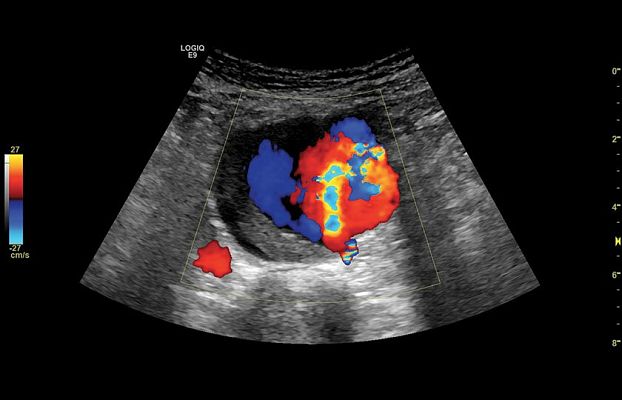

Клинические изображения

Исключительная универсальность и качество визуализации

Задачи, лежащие в сфере общей визуализации весьма широки, и врачам ежедневно приходится вести прием большого числа пациентов, и проводить диагностику различных заболеваний. Пациенты могут быть разного возраста, от новорожденных до престарелых, и иметь разную массу тела, в том числе избыточную. Всё это не должно быть помехой для качественной и достоверной диагностики.

LOGIQ E9 имеет невероятно широкий спектр применения, который включает исследования брюшной полости, сердечно-сосудистой системы, органов репродукции, скелетно-мышечного аппарата, малых органов и структур, мочевыделительной системы, транскраниальные исследования у взрослых и детей.

Экспертное качество визуализации системы LOGIQ E9 является основой для оперативного получения клинически важной информации, что в свою очередь необходимо при принятии обоснованных решений. Передовые функции, такие как объемная навигация, эластография компрессионная и сдвиговой волны, исследования с контрастными веществами и визуализация в режимах 3D/4D ещё больше расширяют возможности для быстрой и точной диагностики, а простой интуитивно понятный интерфейс, инструменты автоматизации и протоколы исследований позволяют максимально оптимизировать рабочий процесс и справится с самой высокой нагрузкой и большим пациентопотоком.

- B-Flow и Color B-Flow — технология прямой недопплеровской визуализации кровотока в режиме реального времени, которая позволяет получить гемодинамический профиль с повышенной чувствительностью и разрешением без нежелательных сигналов от окружающих тканей в сосудах всех типов, от крупных, например, сонной артерии, до мелких, например, сосудах паренхиматозных органов.

- Контрастно усиленный ультразвук (CEUS) — использование контрастных препаратов для повышения чувствительности при визуализации кровотока в сосудах.